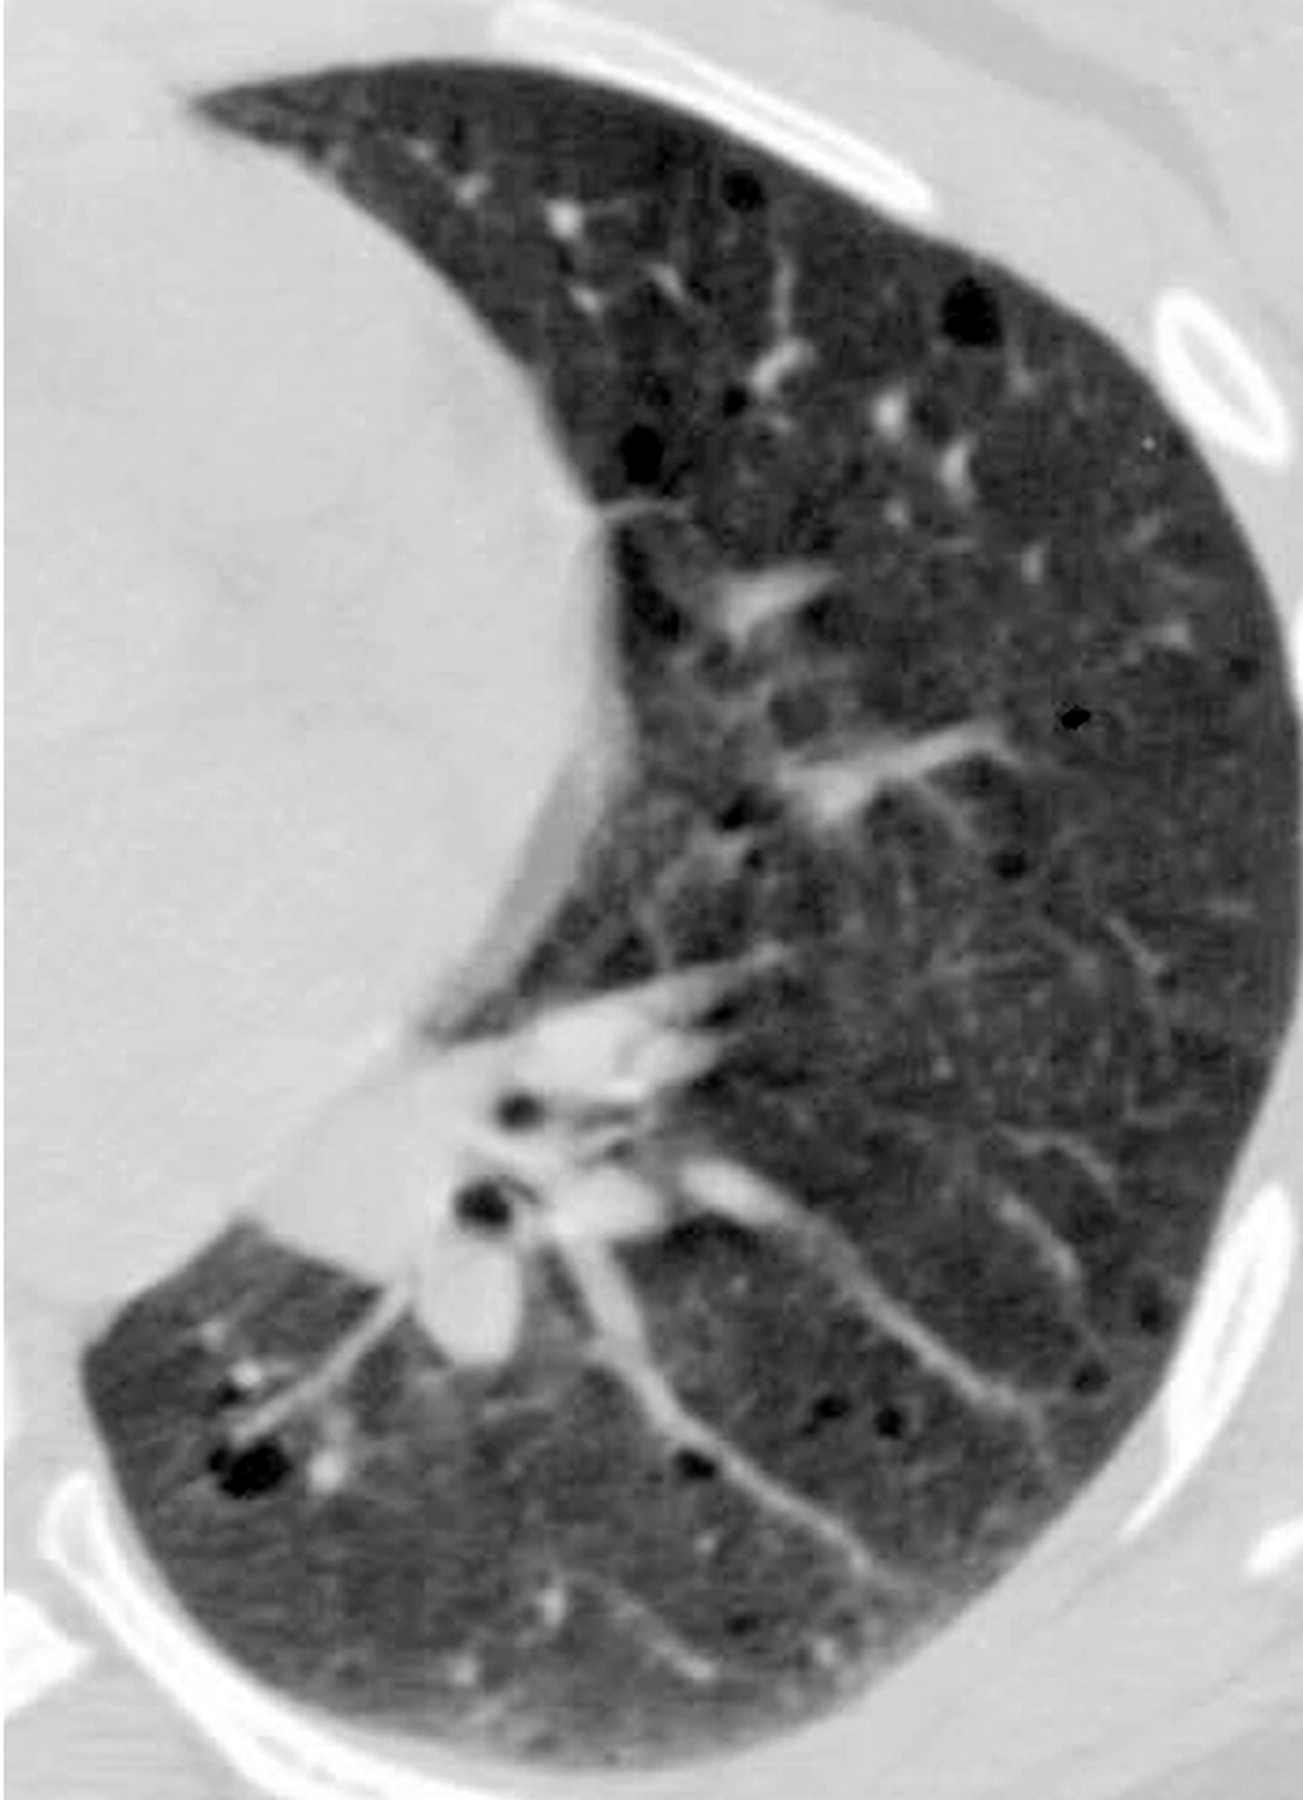

лимфангиолейомиоматоз

Типичный пример патологии при которой основным патерном являются кисты - :

Пневмоторакс как осложнение. может даже клапанный? пневмония ("матовое стекло") с ателектазами? в нижней доли справа

Лимфангиомиоматоз.

Из архива AFIP. Лимфангиолейомиоматоз.